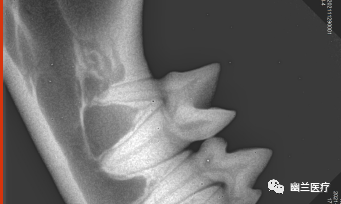

● 牙科DR可用于宠物牙科拍片诊断:牙髓病、牙周病、猫牙吸收等,可以拍摄犬、猫、马等动物,操作简单,安全,可以满足宠物不同的临床需求。

● 图像比普通X光照片更清晰,更易发现病变,从而减少漏诊和误诊。

07

案例分享